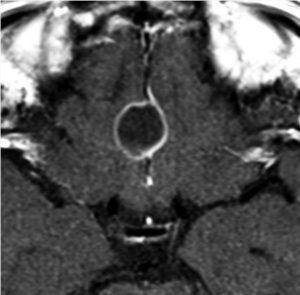

4歳の時に頭蓋咽頭腫に対して50グレイの分割照射を受けました。両側の内頸動脈と前交通動脈が被曝しています。16歳(12年後)に左片麻痺の虚血発作を生じました。右内頸動脈が閉塞してウィルス動脈輪閉塞(モヤモヤ病)になっていました。前交通動脈に動脈瘤(赤矢印)もできていました。小児の頭蓋咽頭腫への放射線治療ではかなり高率に閉塞性脳血管障害を生じるのですが,治療後10年以上がたってから起るので,治療を行った医師はそれをみることはほとんどありません。